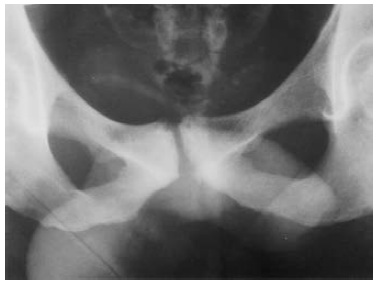

Podemos realizar una primera aproximación diagnóstica solicitando una radiografía de pelvis, con proyecciones anteroposteriores y axiales, por su facilidad y coste a la hora de realizarse. Comúnmente, evidenciaremos esclerosis subcondral, irregularidad de la sínfisis y resorción ósea, en casos avanzados (Figura 1).8 La prueba que mayor información nos va a aportar será la resonancia magnética (RM). Será frecuente encontrarse un edema medular difuso, el cual se extiende desde la superficie subcondral, que a menudo involucra ambas ramas púbicas.9 Además, se suelen encontrar signos de periostitis, irregularidades de las superficiales articulares, erosiones, osteofitos anteriores y posteriores y quistes subcondrales. El signo de la herradura está comúnmente presente (Figura 2). Las uniones miotendinosas se conservan, a menos que haya tendinopatía coexistente.9

Se seleccionaron dos pacientes de 65 y 72 años. Ambas presentaron dolor en la sínfisis que les limitaba las actividades de la vida diaria. Una de ellas realizaba actividad física moderada que había tenido que cesar por completo debido a las molestias continuas. Se realizaron estudios de imagen que comenzaron con radiografías simples de pelvis (Figura 3).

Figuras 3: Radiografía flamenco y anteroposterior. Imágenes correspondientes a las pacientes de nuestra serie. En ambas se pueden apreciar cambios degenerativos que afectan al hueso subcondral con irregularidad y disminución del espacio de la interlínea articular.